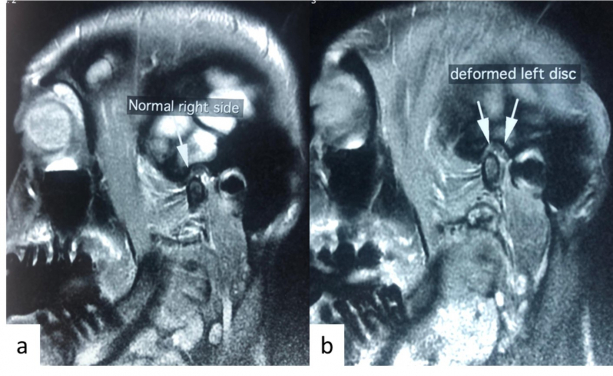

牙骹位於耳朵前方。用手指輕按那處的凹位並開合嘴巴,便會感覺到顳下頜關節(牙骹)移動。牙骹痛源於肌肉或關節問題,前者多因肌肉勞損例如經常嘴嚼香口膠、魷魚絲或果仁等黏韌堅硬食物,或睡覺時有磨牙或咬緊牙關的習慣。後者則有機會是關節軟骨移位發炎導致 -「顳下頜關節綜合症」,其一般症狀乃「開口埋口」說話、吞嚥、打呵欠時感覺牙骹痛,有時會聽到顎骨「卡卡」聲,牙骹不能順暢開合,痛楚可延伸至面部、頭、耳和牙齒等。

關節性牙骹痛通常由保守治療開始,例如處方消炎藥、物理治療、進食柔軟食物,和使用咬合夾板(牙膠)減輕關節疼痛和改善張口度。當保守治療效用不顯著時,醫生會嘗試進行顳下頜關節沖洗術的微創療法,方法是在顎關節放入兩枝針,灌入生理鹽水沖洗關節,把發炎物質和纖維組織沖走,減低關節負壓力,亦可注入透明質酸潤滑關節。顳下頜關節沖洗術在90年代起開始普及,其風險低,成功率高達80至85%。